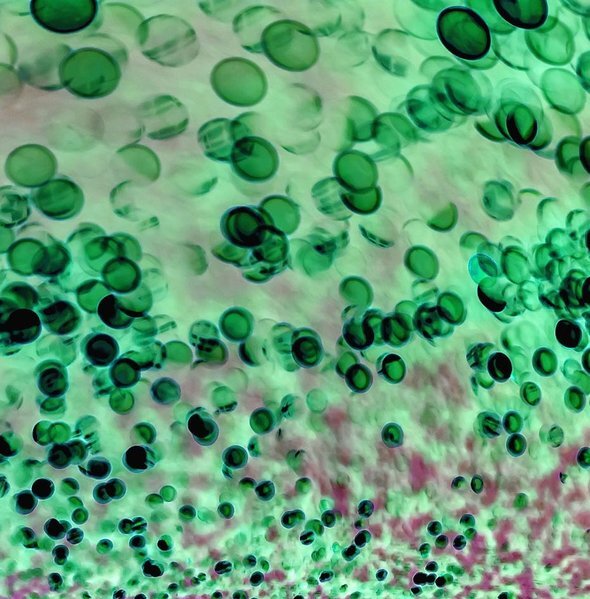

• характерные изменения в клиническом анализе крови.